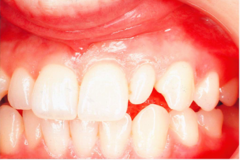

"pregnancy tumor" a)gingival hyperplasia b)papillary hyperplasia of the palate c)epulis fissuratum d)pyogenic granuloma

Front

pyogenic granuloma- granulation tissue in response to local irritant

Back